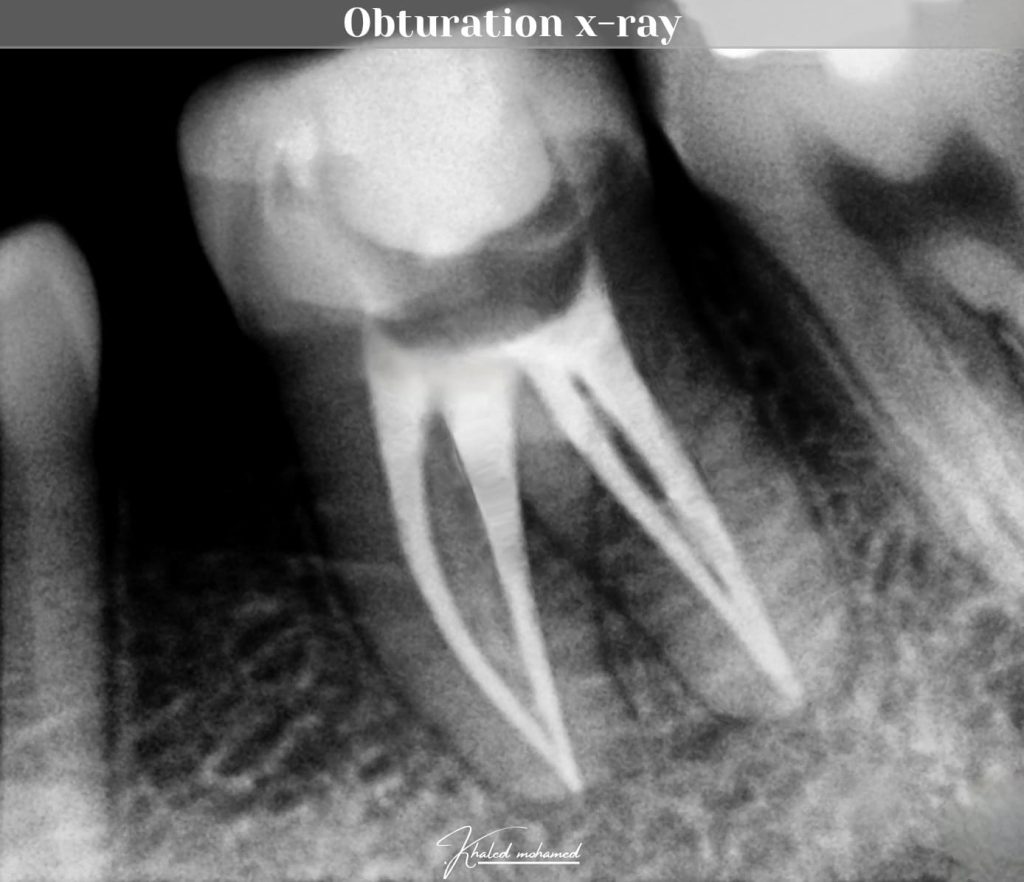

Obturation x-ray